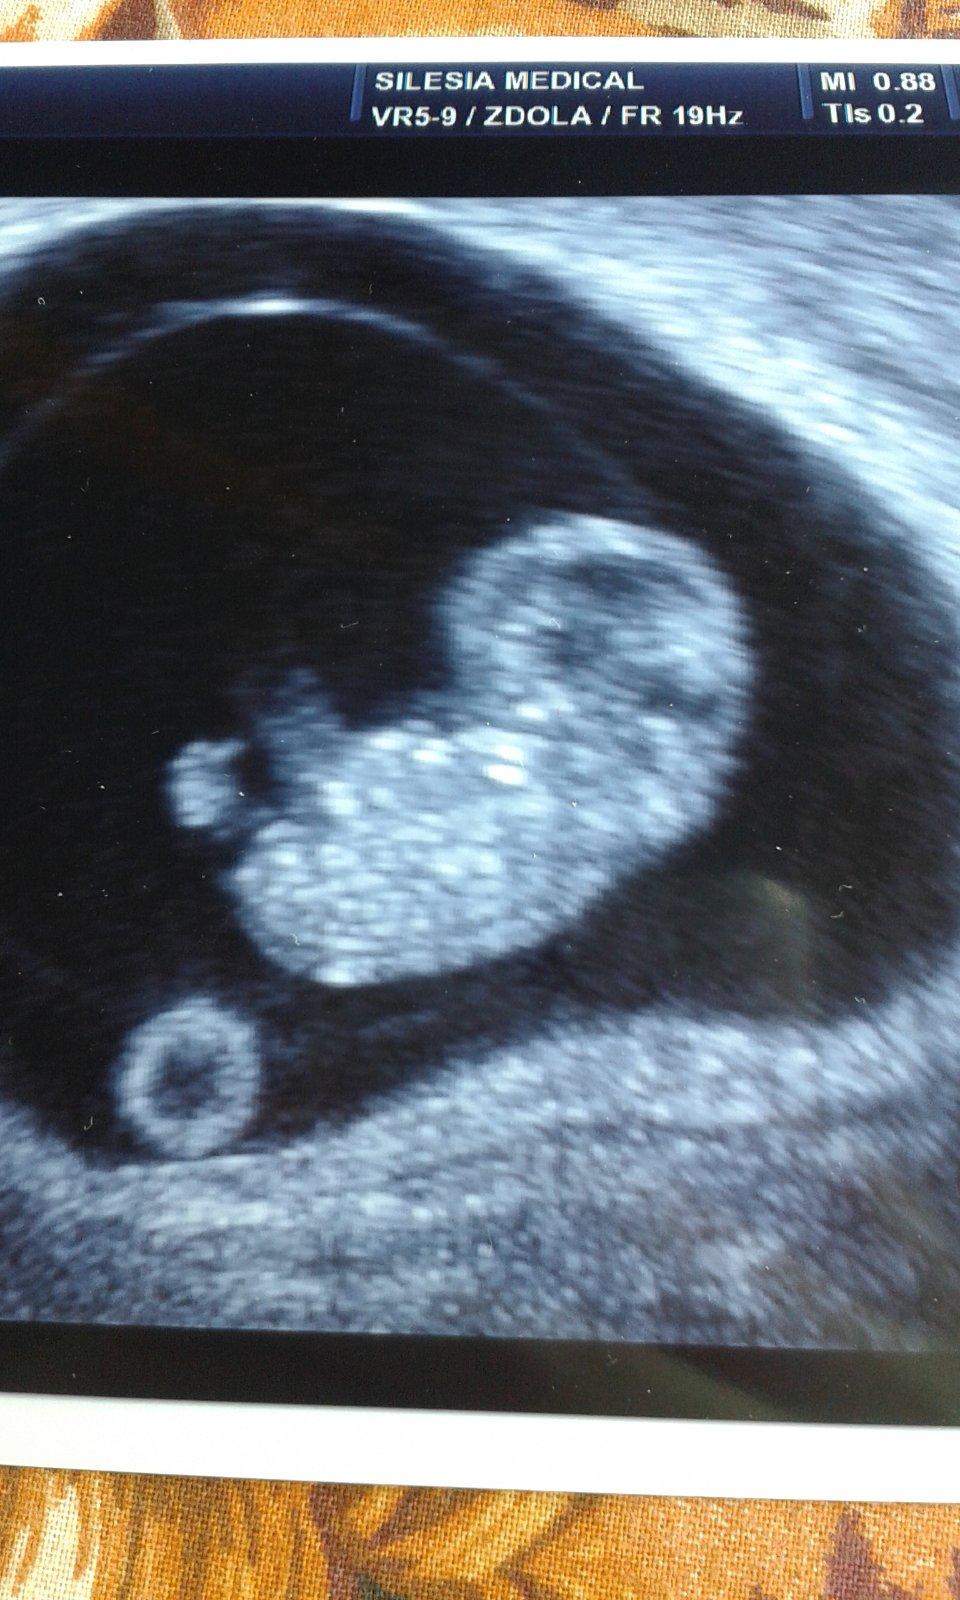

8+4 tt, bije srdicko, měří 2,1 cm